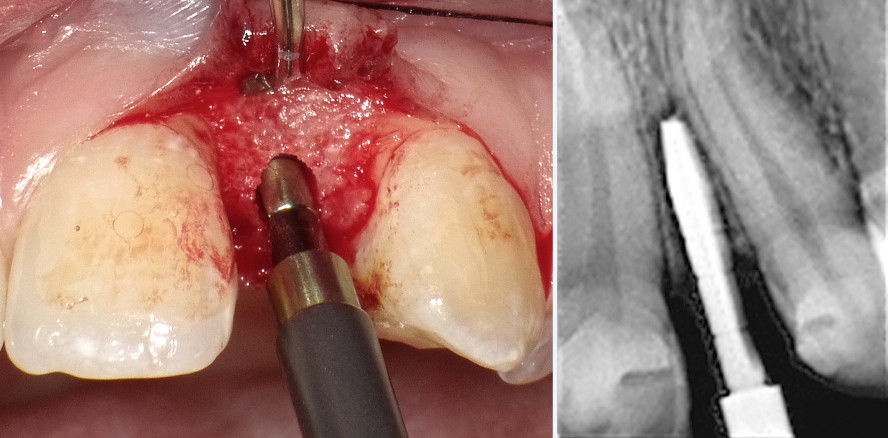

Bei der interproximalen Spreizungstechnik werden die benachbarten Wurzeln in einem engen interradikulären Raum mit einem speziellen Instrument sanft weggedrückt. Die Handbohrer (Bicon) haben eine vertikale Schneidekante, die in einer scharfen Spitze ausläuft. Die Handbohrer werden manuell mittels eines geraden Multifunktionsgriffs in die initiale Osteotomie gedrückt. Diese Osteotomie wird mit einem normalen Pilotbohrer mit 2 mm Durchmesser (1.100/min) durchgeführt und ist nur 3 bis 4 mm tief. Hochgeschwindigkeitsbohrer wirken in diesen Fällen traumatisch, weil sie das parodontale Ligament überhitzen und versehentlich eine der Wurzeln beschädigen könnten. Die initiale 2 mm breite und 3 bis 4 mm tiefe Osteotomie reicht aus, um den Handbohrer mit einem Durchmesser von 2,5 mm zwischen die Wurzeln gleiten zu lassen, wobei zu beachten ist, dass erstens die Bohrerspitze 3 mm apikal verjüngt ist, und daher dünner ist als der Durchmesser des Bohrerkörpers, und zweitens die Schneidekante nur dazu verwendet wird, sich ihren Weg entlang der dickeren Gaumenplatte zu bahnen. Die runde, nichtschneidende Oberfläche des Handbohrers wird über die glatte Spongiosa und zwischen die beiden Wurzeln gedrückt, ohne diese zu beschädigen. Dies ist möglich, weil bei diesem Verfahren kein Drehmoment angewendet und nicht geschnitten wird. Der finale Handbohrer mit einem Durchmesser von 3 mm wurde ebenfalls in die Osteotomie gedrückt und zwischen die Wurzeln geführt. Auf den geraden Handgriff wurde ein kontinuierlicher und langsamer Druck ausgeübt. Manchmal wird die Hilfe eines Hammers benötigt, um den Handbohrer 10 bis 11 mm vom Alveolarkamm nach unten zu bewegen (Abb. 3 und 4). Das Implantat wurde mit einem speziellen Instrument eingebracht, das es dem Chirurgen erlaubt, das Implantat mit festem und präzisem Druck in die zuvor vorbereitete Osteotomie zu drücken (Abb. 5). Der letzte Schritt war das abschließende Einklopfen mit dem Hammer unter Verwendung der auf den geraden Griff montierten Insertionsspitze. Das durchmesserreduzierte Implantat wurde daher zwischen den beiden Wurzeln komprimiert (Abb. 6). Das Implantat mit einem Durchmesser von 3 mm und einer Länge von 8 mm wurde mit Druck in die fertige Osteotomie-Höhle eingebracht und mit der Insertionsspitze und dem Hammer 3 mm tief in den krestalen Knochen eingeklopft (Abb. 7). Nach sechs Monaten Einheilzeit wurde der zweite Eingriff durchgeführt und der Implantatschacht freigelegt. Zur Aufnahme der provisorischen Kronen wurde ein Abutment mit einem Schaft von 2 mm Durchmesser und einer hemisphärischen Basis von 4 mm Durchmesser gewählt. Es ist von größter Wichtigkeit, das Weichgewebe um das entsprechende Kronenprofil herum einheilen zu lassen. Dies kann durch Änderung des Emergenzprofils der provisorischen Krone erreicht werden, bis sich die Papillen ausgebildet haben. Nachdem das Weichgewebe vollständig ausgeheilt war, wurde die finale Abformung genommen und die definitive Krone auf die Titanabutments zementiert (Abb. 8 und 9).